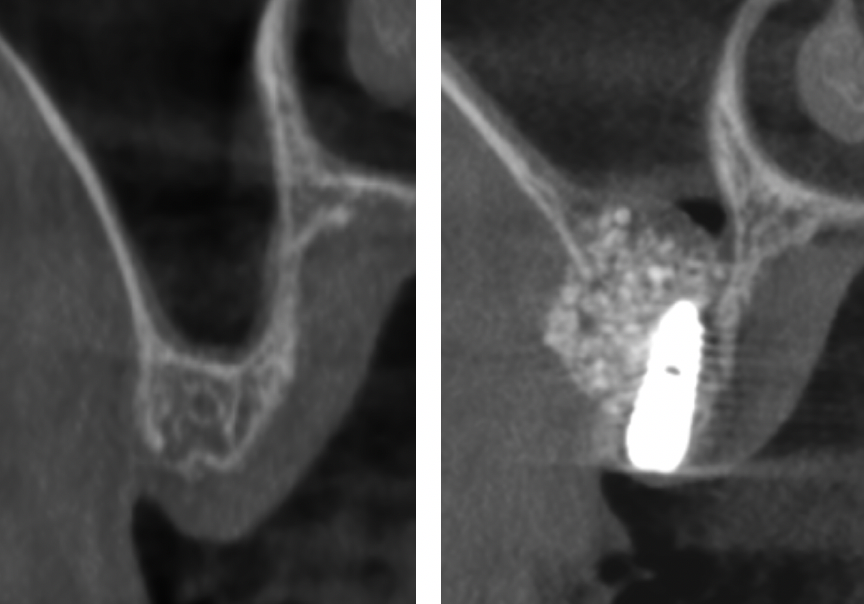

O altă situație frecventă este pierderea înălțimii osoase în zonele laterale maxilare, zone în care în imediată vecinătate se află sinusul maxilar, o cavitate pneumatică cu rol în respirație. În această situație medicul trebuie să reconstruiască defectul osos vertical astfel încât oferta osoasă să fie corespunzătoare, intervenție denumită „Sinus lift” (Fig. 7.4.3). De asemenea și în acest caz sunt situații în care implantul se poate aplica imediat sau după un anumit timp de vindecare.

Figura 7.4.3 Recuperarea înălțimii osoase prin „sinus lift” extern și aplicarea implantului în aceeași intervenție chirurgicală